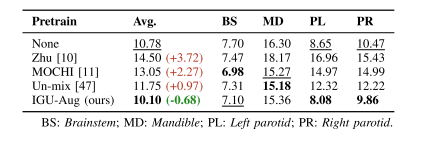

TABLE IIIANALYSIS CONDUCTED ON CEPHALOMETRIC DATASET.COMPARISON OF OTHER PIXEL-WISE SSLFOR local Feature Matching

表 3 头影测量数据集 上的分析:本文方法与其他逐像素自监督学习(SSL)方法在局部特征匹配任务中的对比